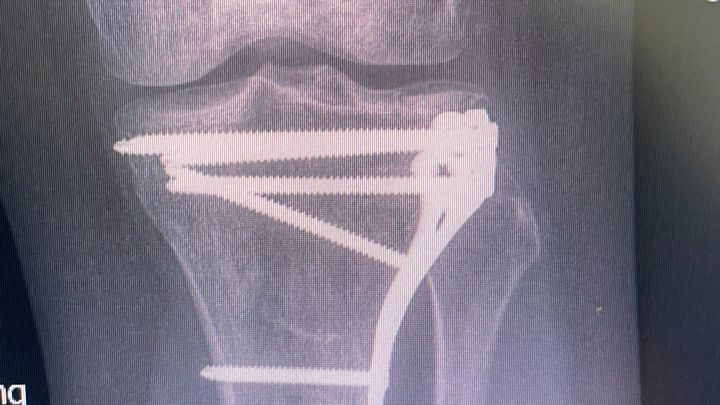

Last May, while I was out dog walking (my job and absolute passion!), one of my clients’ dogs accidentally crashed full speed into my leg. The impact was so strong it fractured my left tibia. I needed orthopaedic surgery to repair the break, and I now have a large metal plate and 8 screws holding my leg together.

Recovery hasn’t been easy. I’ve done everything I can to heal and get back to normal, but the metal hardware has been causing ongoing pain, discomfort, and limited mobility. My doctor has said I’m now eligible to have the plate and screws removed (YAY) — something I’ve been looking forward to for months.